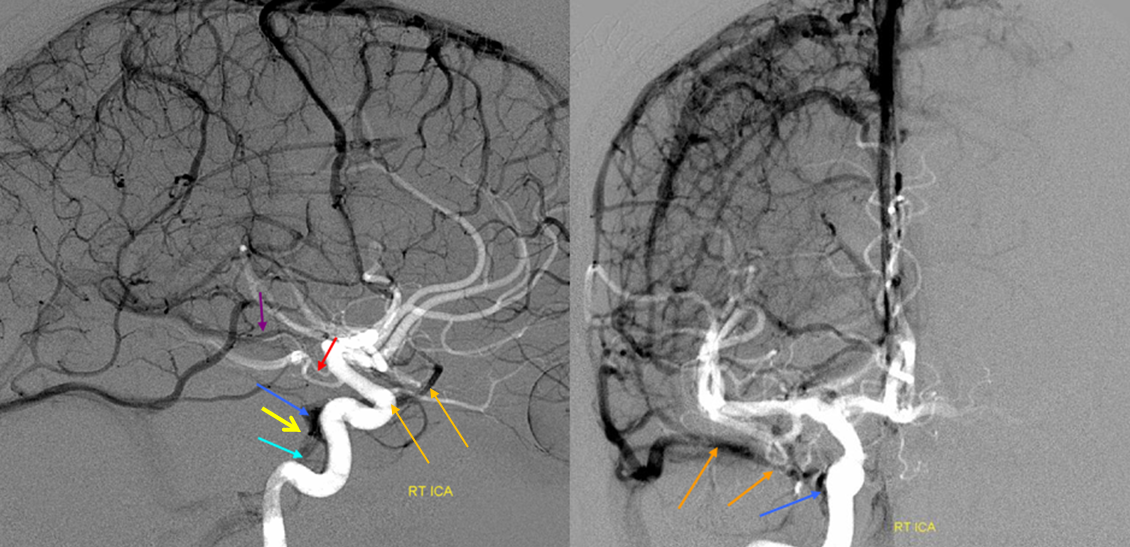

Анатомия внутренней яремной вены: КТ изображения